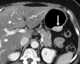

Sclerosing cemental mass